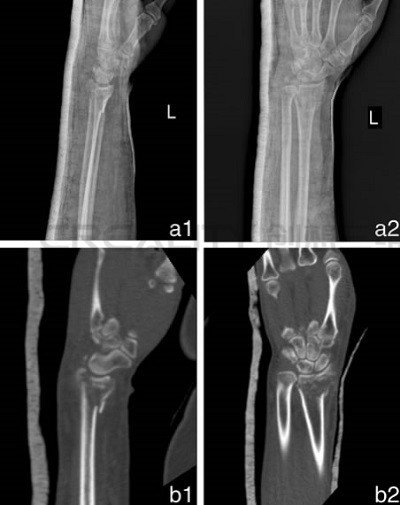

3D打印機制造模型如何改善骨折治療

中國研究人員正在研究使用3D打印機制造模型來改善骨折治療。第二附屬醫院骨科和浙江溫州醫科大學育英兒童醫院的華晨在“使用3D打印機制造的模型來改善骨折治療功效&rd...